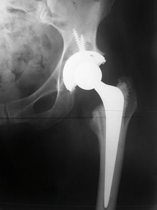

My hip replacement came as quite a shock. The left hip had been getting worse, I thought that I had injured it and that it would heal, in time.

The x-ray confirmed my doctor's prognosis. But instead of going on the waiting list I went private and chose The Nuffield group.

A day later and I was having my new hip x-rayed. It's not like x-rays of old, it's now digital, the image is an actual image. I saw my own hip on the computer screen. "Is it possible to have a copy of that?" I asked the radiographer. "Give me your phone number," she replied. Once back in my room I saw a text message on my phone, a picture message. It's my hip replacement. I was discharged the following day, but I heeded medical advice and didn't return to work for twelve weeks.